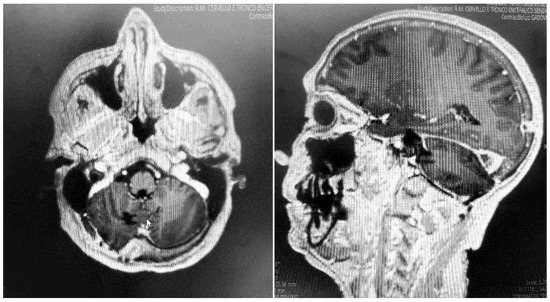

The patient underwent an early postoperative MRI, which documented the complete resection of the lesion without any postoperative complications (Figure 4). The patient was discharged with a significant improvement in the neurological examination at 7 days after surgery. Histopathology confirmed a diagnosis of meningioma, WHO grade 1, subtype fibrous.

Figure 4. Postoperative MRI + c: these pictures show the gross total resection of the lesion with no signs of postoperative complications.